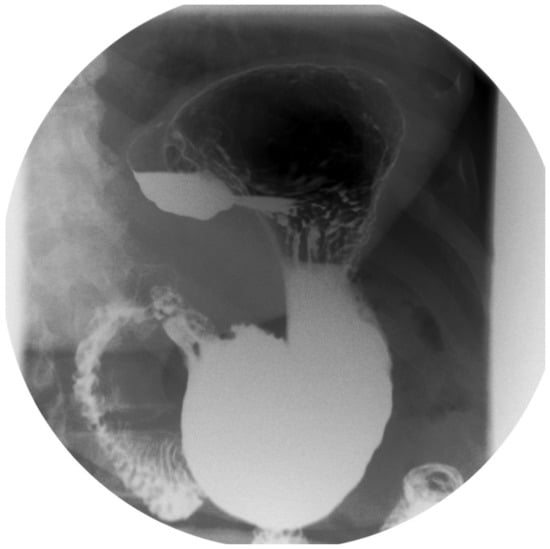

- After the transoral position of a bougie (of diameter ranging 36–40 Fr), sleeve gastrectomy is performed with the use of a stapler, beginning from the distance of 4–6 cm from the pylorus up to the angle of His.

- The staple line should be regular and straight from the antrum to the angle of His.